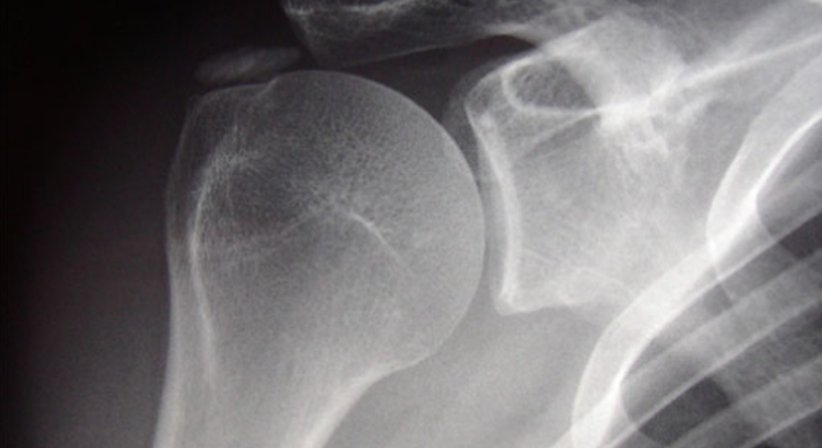

Die Schulter ist das komplexeste Gelenk des menschlichen Körpers. Bänder, Muskeln, mehrere "Zwischengelenke",Schleimbeutel,und Sehnen ermöglichen in kompliziertem Zusammenspiel Beweglichkeit in allen 3 Ebenen de Raumes.